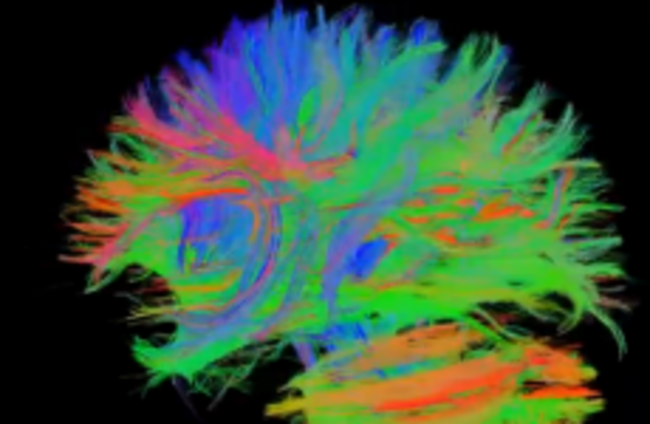

An MRI scan of the brain. Chinese researchers have found evidence that internet 'addiction' can cause the links between parts of the brain to be frayed. jgmarcelino via Flickr

The study published in the PLoS One journal yesterday compared brain scans of young people who consider themselves ‘addicted’ to the internet with those of a ‘healthy’ control group, and discovered that heavy users had damaged fibres connecting certain parts of the brain.

MRI scans on the 17 ‘addicted’ people showed damage to the ‘white fibres’ – nerves between the areas of the brain controlling emotional reasoning, decision-making, self-control and attention.

The study is thought to the first time that excessive use use of the internet, or engagement in video games, has been shown to cause changes in the brain’s ‘white matter’.